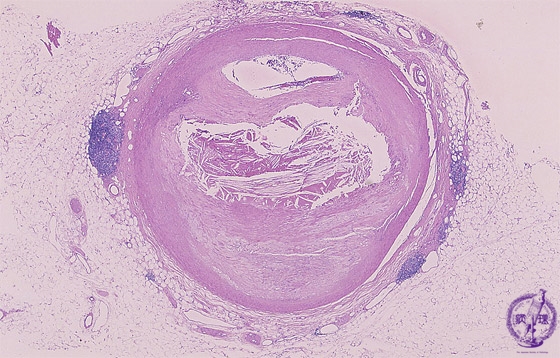

Microscopic view (HE, low power view): There is severe stenosis of the coronary artery due to atherosclerosis demonstrated here by eccentric intimal wall thickening and extracellular lipid deposition.